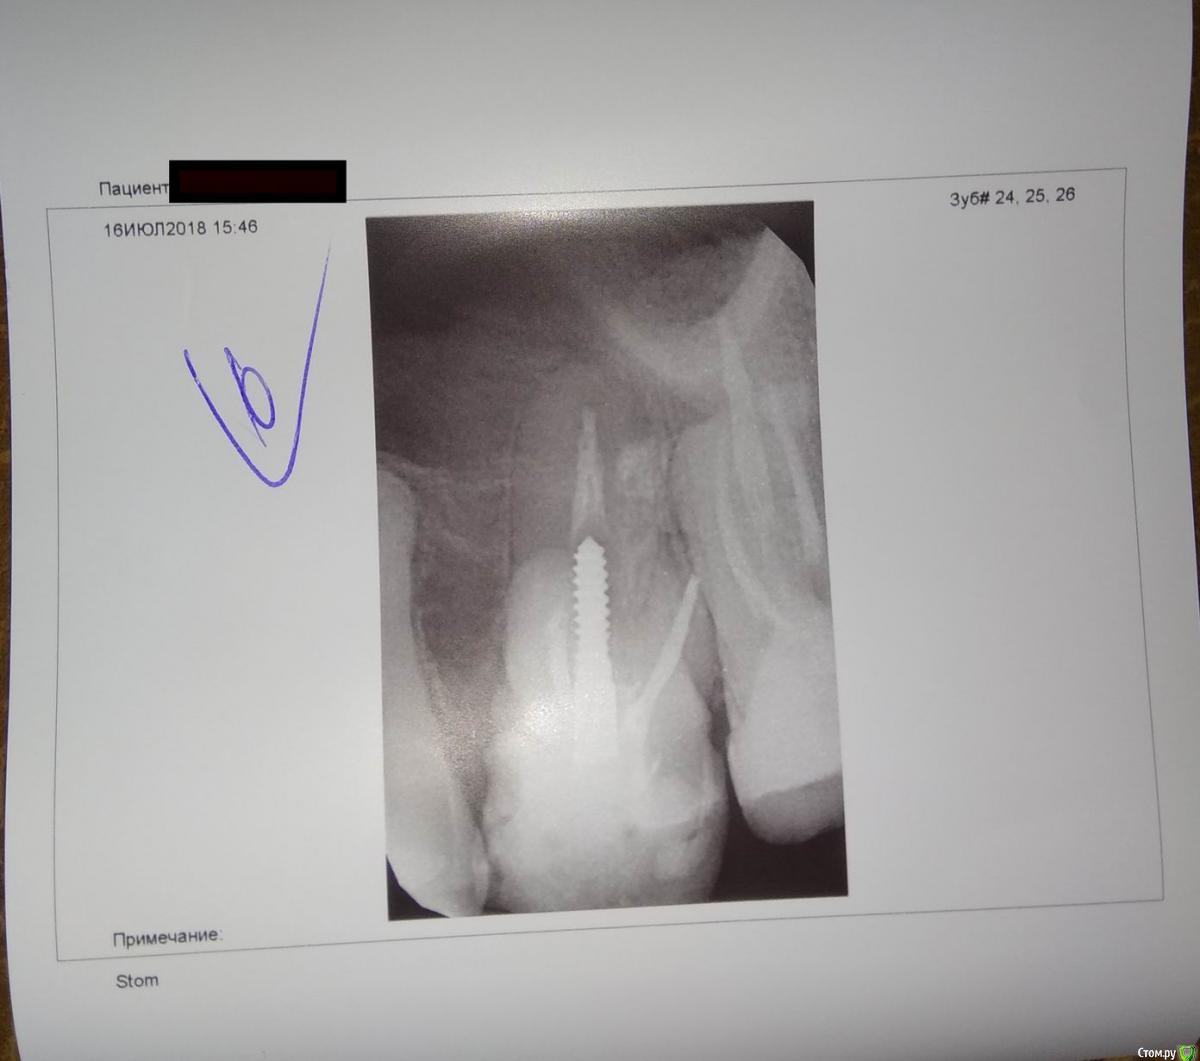

Остро заболел шестой зуб на верхней челюсти, в районе корня. Десна немного распухла.

Сделали снимки радиовизиографом - терапевт сказал, что вроде для него работы нет.

И по результату КТ - направили к хирургу на удаление 6 и 7 зубов...

Хирург говорит - удалять шестой.

Можно и нужно ли пытаться его вылечить без удаления?

post-55588-0-13418000-1532456619_thumb.jpgpost-55588-0-34704800-1532456739_thumb.jpgpost-55588-0-69223700-1532456746_thumb.jpgpost-55588-0-37543000-1532456752_thumb.jpg